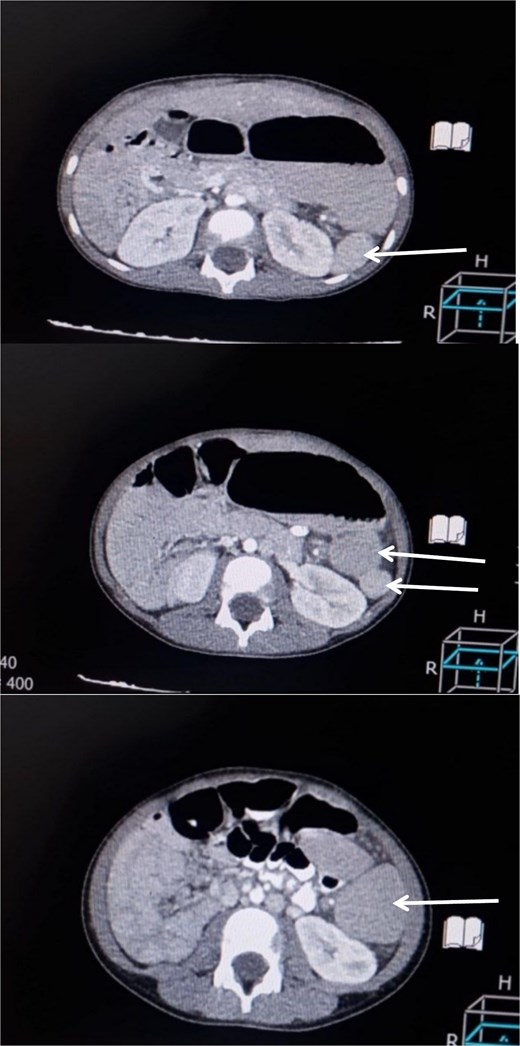

A 6-year-old boy presented with a 2-day history of abdominal pain, vomiting, and diarrhea. The pain was of sudden onset, severe, intermittent, mainly in the umbilical region, not radiating anywhere, with no aggravating or relieving factors. It was associated with non- bilious vomiting of small amounts of food contents, in addition to small amounts of diarrhea not containing mucus or blood. Upon admission, the patient looked unwell but not febrile. His pulse rate was 100 beats/min, and the respiratory rate was 24 breaths/min. Abdominal examination revealed a firm, non-tender mass, ~8 × 4 cm in diameter with a smooth surface, palpable just left of the umbilicus. Laboratory investigations were unremarkable. An abdominal ultrasound was performed initially that showed a well-defined, 10 × 4 cm homogenous mass, seen at the midline and extending to the left of the midline suggestive of an enlarged spleen. As the ultrasound was inconclusive, a contrast-enhanced CT abdomen was obtained, which demonstrated multiple spleen-like densities in the left upper and lower abdominal quadrants with minimal free fluid in the left iliac fossa (Fig. 1).

Contrast-enhanced CT scan of the abdomen demonstrating multiple spleen-like densities (arrows) can be seen in the left upper and lower quadrants of the abdomen.